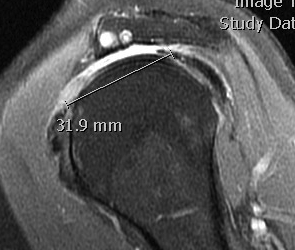

MRI

Measure tear in the coronal and sagittal plane

Massive rotator cuff tear of the supraspinatus and infraspinatus tendon - retracted to glenoid

MRI predictors of reparability

- 60 patients with large and massive tears

- irreparability associated with retraction to or beyond glenoid

- irreparability associated with tangent sign / advanced fatty infiltration / superior migration humeral head

- 120 patients with large and massive tears

- irreparability associated with modified grade III Patte (retraction to medial 5th humeral head)

- associated with 94% chance or irreparability

- irreparability also associated with reduce acromiohumeral distal / superior migration humeral head

Examples of rotator cuff tears that are likeley irreparable